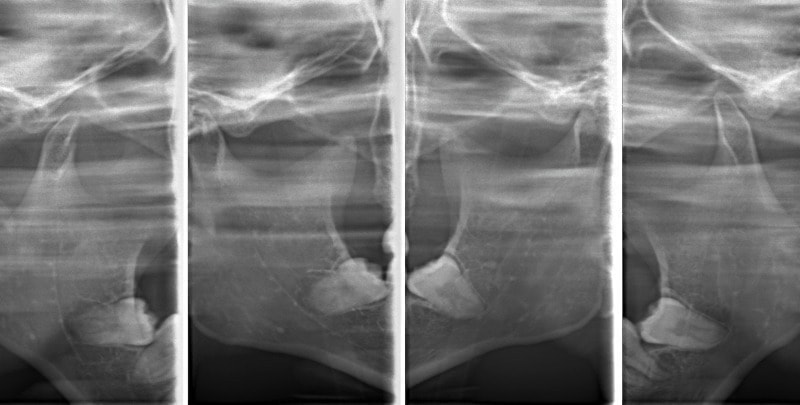

検査時顎関節

非対称のケースによくみられる、顎関節の変形や、CO-CRの不一致、位置の不正が認められます。